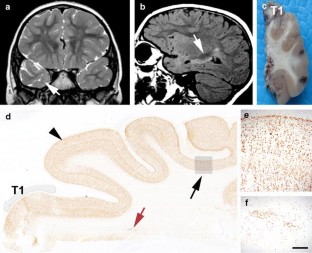

Focal Cortical Dysplasias (FCDs) are highly epileptogenic brain lesions and are a frequent cause for drug-resistant focal epilepsies in humans. FCDs present with variable histopathological patterns, including architectural, cytoarchitectural or white matter abnormalities. Pathomechanisms compromising neuroblast proliferation, migration, or differentiation are likely to play a role in the etiology of FCD variants. FCDs were subsumed, therefore, into the broad spectrum of malformations of cortical development. The most frequent subtype comprises FCD Type II, which in general occurs as isolated lesion in extratemporal location and is histopathologically characterized by dysmorphic neurons (Type IIA) and balloon cells (Type IIB). Neuroimaging hallmarks include hyperintense T2-signaling and a “transmantle sign”. Electrophysiological recordings show peculiar interictal spike patterns and complete surgical resection results in favorable seizure control. In contrast, FCD Type I can be identified in young children with severe epilepsy and psychomotor retardation. Parietal, temporal, and occipital lobes may be involved in seizure generation, although neuroimaging often reveals normal contrast intensities. Surgical resection strategies ameliorate seizure frequencies in many children, whereas complete seizure relief can be achieved only in rare cases. According to the currently used FCD classification system, the same histopathological FCD Type I variant can be diagnosed as associated lesion in the large cohort of epilepsy patients with hippocampal sclerosis, low-grade glio-neuronal tumors, vascular malformations, or glial scarring. MRI is often not helpful to detect the dysplastic cortical areas. In addition, there is no specific electrophysiological pattern for an associated dysplastic lesion. Surgical resection of the epileptogenic area results, however, in favorable seizure control. These findings argue for a revised neuropathological classification system that distinguishes isolated versus associated FCD variants to obtain a better correlation with electro-clinical findings and prediction of postsurgical seizure control.

Fig. 2